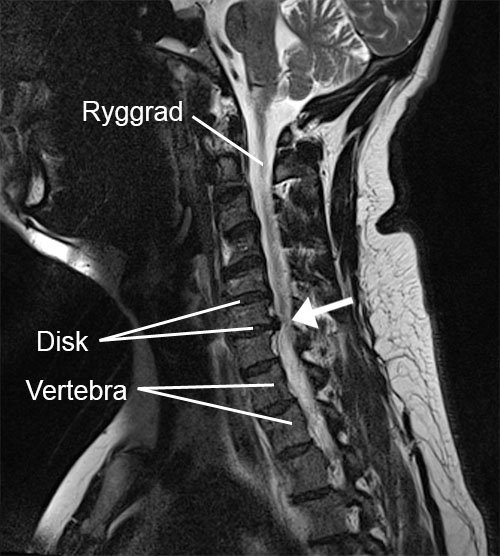

Den øverste delen av ryggsøylen, den "cervikale ryggsøylen", er dannet av nakkevirvlene. Disse er stablet oppå hverandre og gir stabilitet til ryggsøylen. Mellom de harde virvlene finnes mykere strukturer. Dette er mellomvirvelskivene, også kalt disci (entall: discus). Disse skivene er noe elastiske og bidrar til støtdemping og bevegelighet i ryggsøylen.

Ryggmargen går vertikalt gjennom ryggsøylen. Dette er en stor bunt nerver som, etter å ha forlatt ryggsøylen, går ut til alle deler av kroppen. I nakken forlater flere nerver ryggsøylen ved hver virvel. De går blant annet til armene og sørger for muskelkontroll og at følesignaler (som smerte) sendes til hjernen.

Ved en myk nakkeprolaps presser en utbulende mellomvirvelskive på en utgående nerverot. Dette kan oppstå plutselig og gi sterke smerter. En myk struktur presser altså på nerveroten.

Når trykket på en nerverot skyldes kvalitetsforringelse (degenerasjon) eller artrose (slitasje) av nakkevirvlene, kalles dette en hard nakkeprolaps. Da blir rommet hvor nerverøttene passerer ut av ryggsøylen gradvis trangere, noe som kan føre til at nerverøttene blir klemt mellom harde benstrukturer.